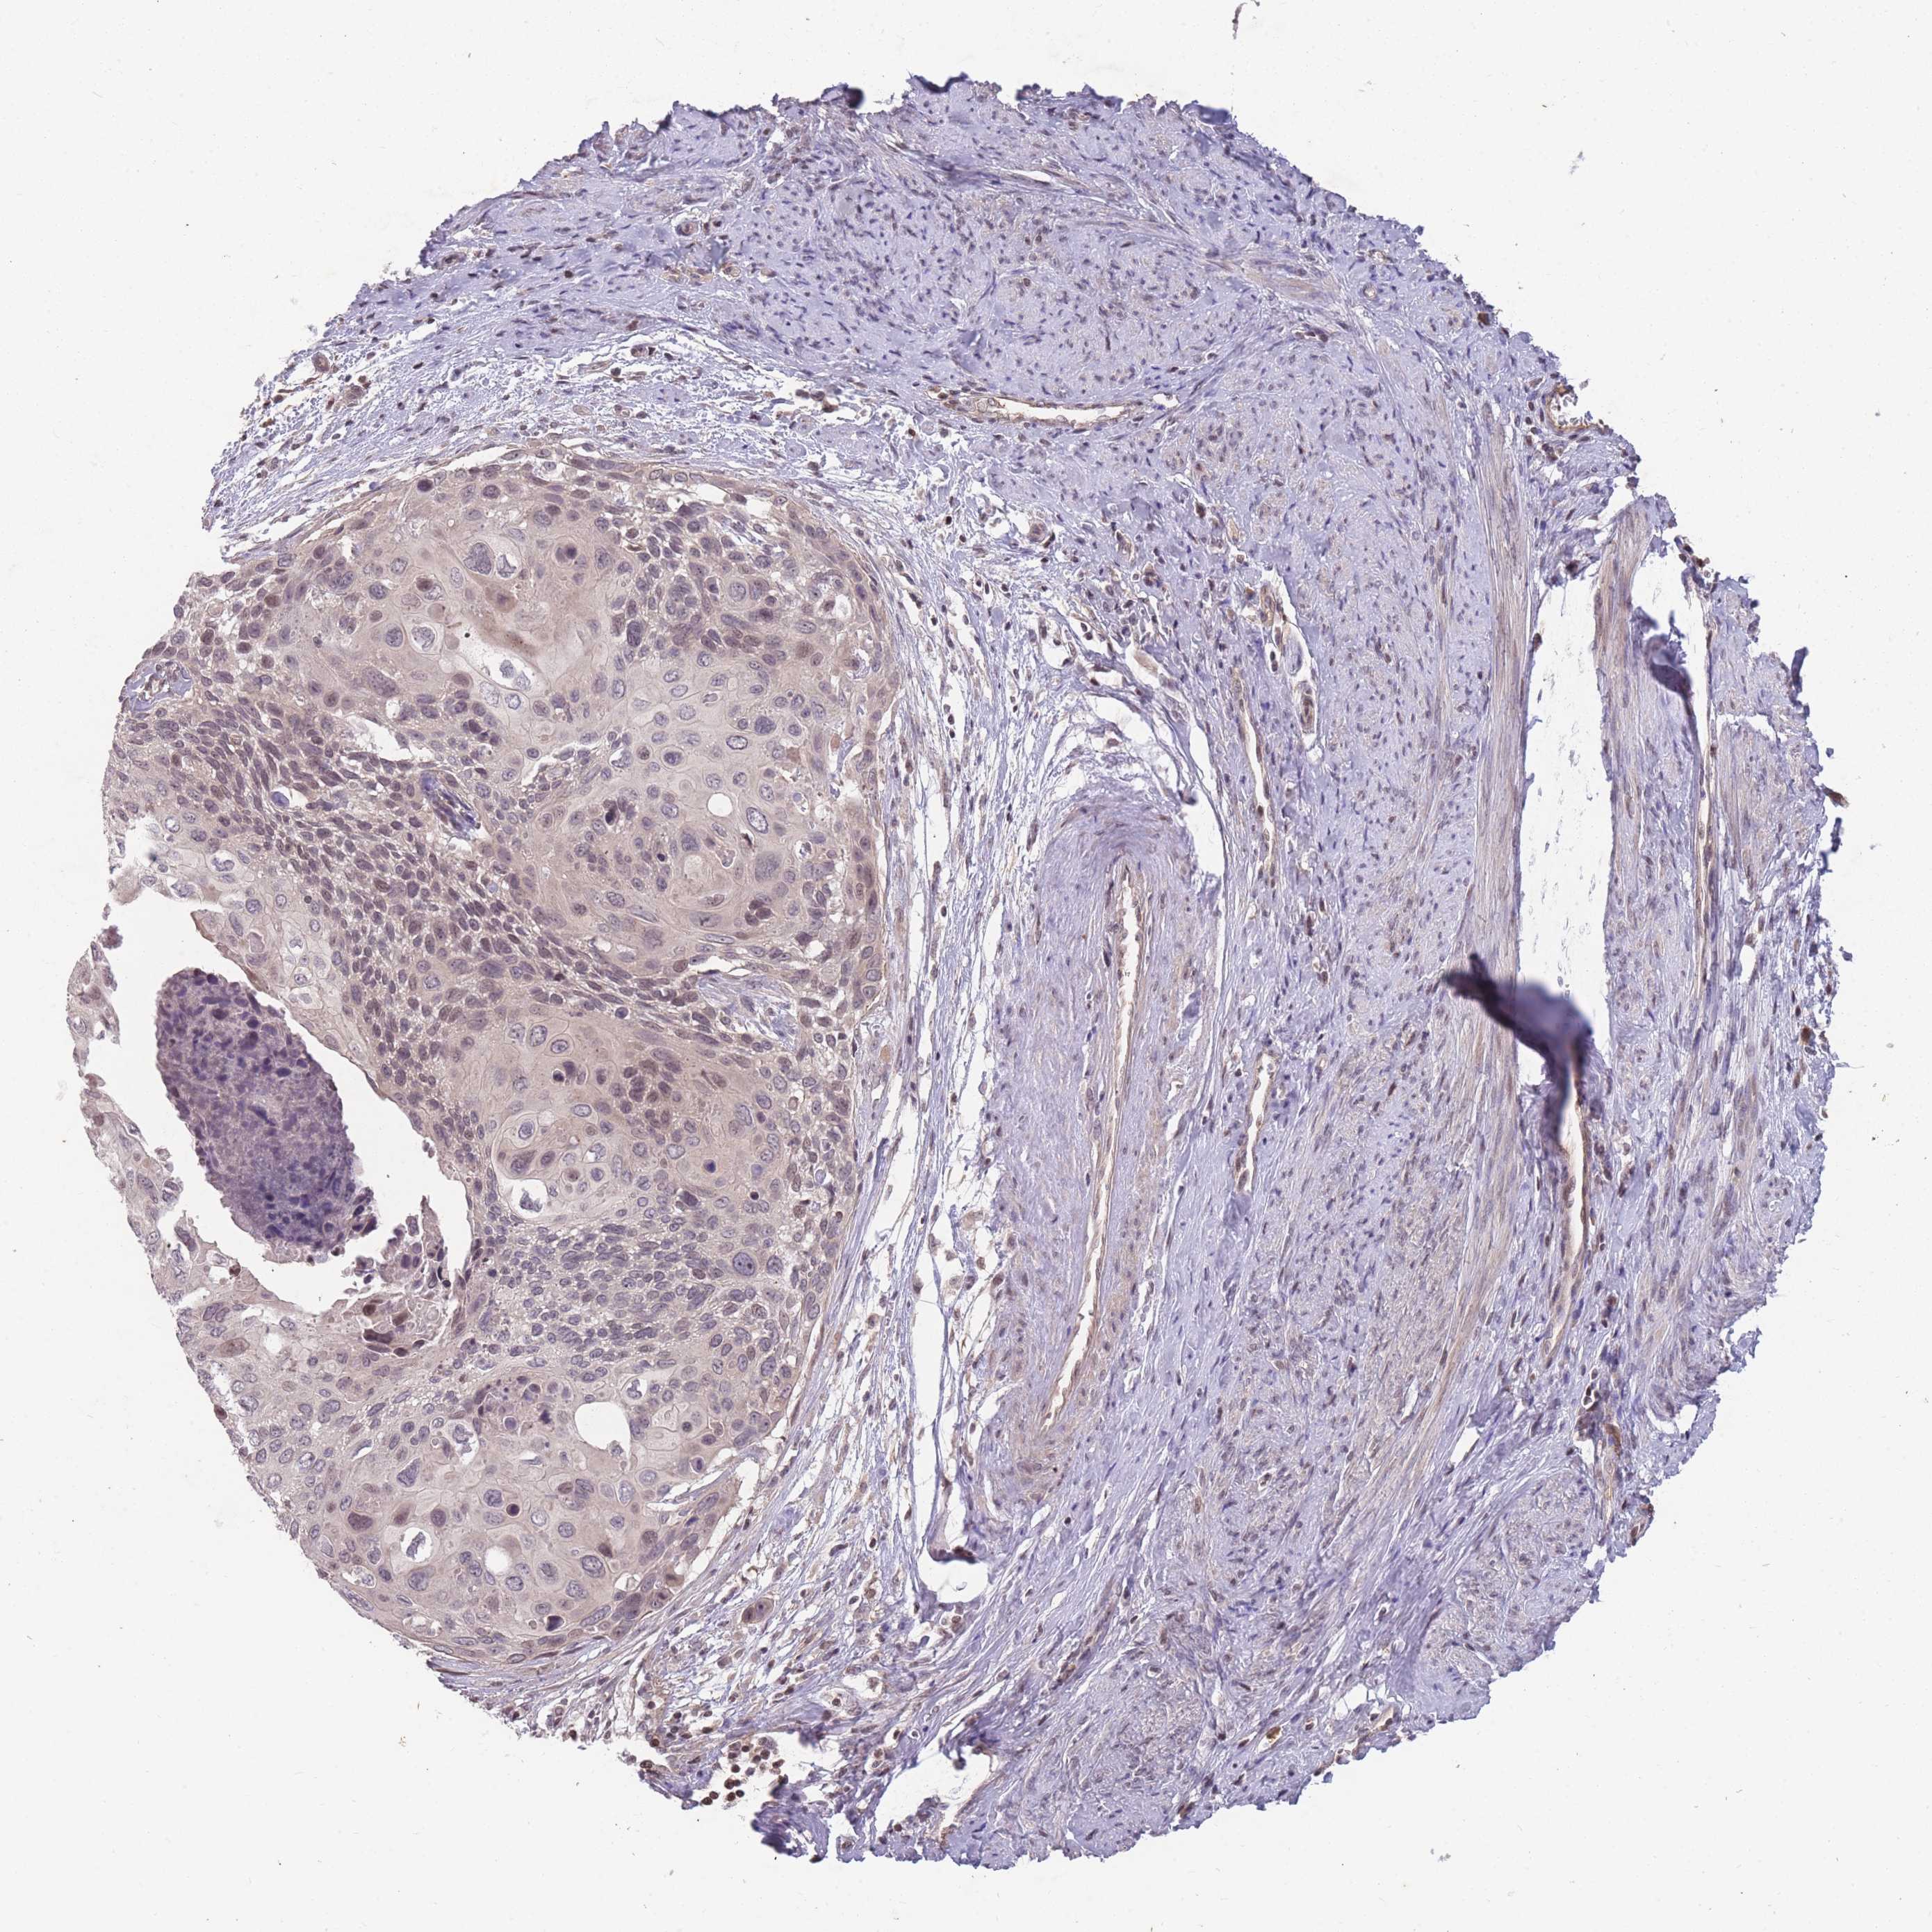

CERVICAL CANCER - Protein expressioni

A mouse-over function shows sample information and annotation data. Click on an image to view it in a full screen mode. Samples can be filtered based on level of antibody staining by selecting one or several of the following categories: high, medium, low and not detected. The assay and annotation is described here.

Note that samples used for immunohistochemistry by the Human Protein Atlas do not correspond to samples in the TCGA dataset.

Antibody stainingi

Antibody staining in the annotated cell types in the current human tissue is reported as not detected, low, medium, or high, based on conventional immunohistochemistry profiling in selected tissues. This score is based on the combination of the staining intensity and fraction of stained cells.

Each image is clickable and will lead to virtual microscopy that enables deeper exploration of all samples and also displays staining intensity scores, fraction scores and subcellular localization as well as patient and tissue information for each sample.

Antibody HPA008121

Antibody CAB032489

Squamous cell carcinoma, NOS

Adenocarcinoma, NOS